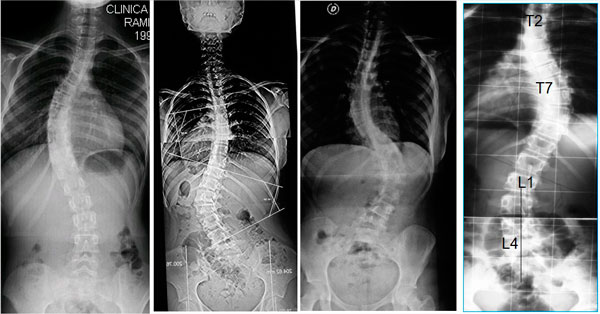

Hemos apreciado signos de escoliosis. ¿Cuál es el siguiente paso?

• Debe ser evaluado por un especialista para una exploración detallada.

• Será preciso realizar una radiografía para confirmar el diagnóstico de escoliosis.

• Las radiografías deben realizarse con el paciente de pie y erguido. Para valorar mejor la alineación global de la columna vertebral, deben incluirse todas las regiones de la columna en una misma placa, en lugar de obtener radiografías individuales de cada región.

La radiografía que debe realizarse se denomina: Espinograma o Columna Panorámica

¿Cómo se ve la escoliosis en la radiografía?

• La escoliosis viene definida por la región de la columna vertebral donde surge la curva (columna torácica alta, columna torácica o columna lumbar).

• La escoliosis puede localizarse en uno o más segmentos: curva simple, curvas dobles o triples.

• La dirección de la curva puede ser derecha o izquierda.

La escoliosis puede localizarse en uno o más segmentos: curva simple, curvas dobles o triples. La dirección de la curva puede ser derecha o izquierda.

Ejemplos de diferentes curvas y diversas localizaciones.